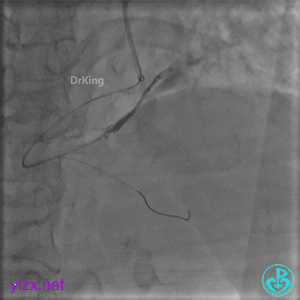

更换6F JR 4.0指引导管,Runthrough NS进入PL分支。

2.0×15mm球囊扩张PL分支开口后PL恢复2级血流。

PL远端血管周围似乎有片状造影剂滞留。

经微导管PL分支造影,该如何解读这个经微导管造影结果?

经指引导管造影。

经微导管造影。